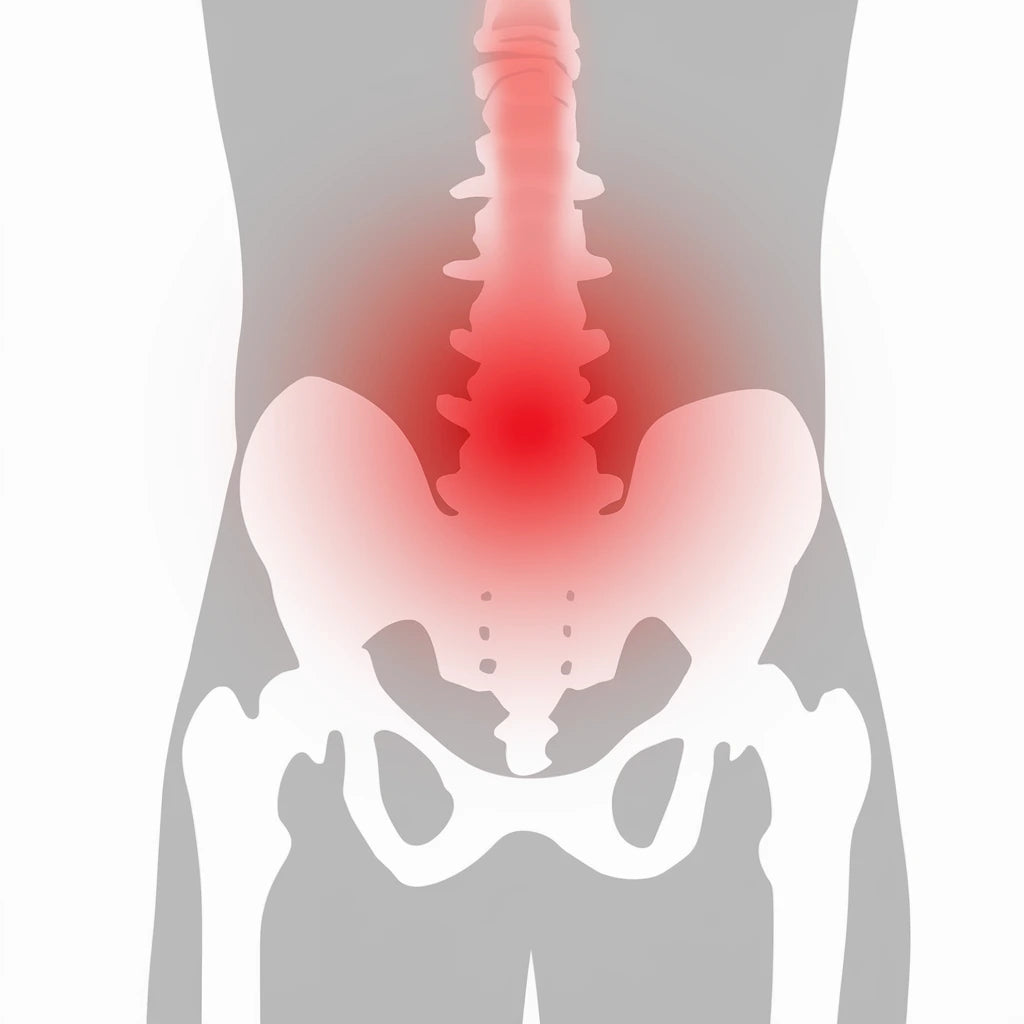

Smärta i ryggen påverkar vardagen för miljontals människor. Den kan uppstå akut eller utvecklas över tid på grund av dålig hållning, skador eller belastning. Här hittar du information om ryggbesvär – från diskbråck till ryggskott och stelhet på morgonen.